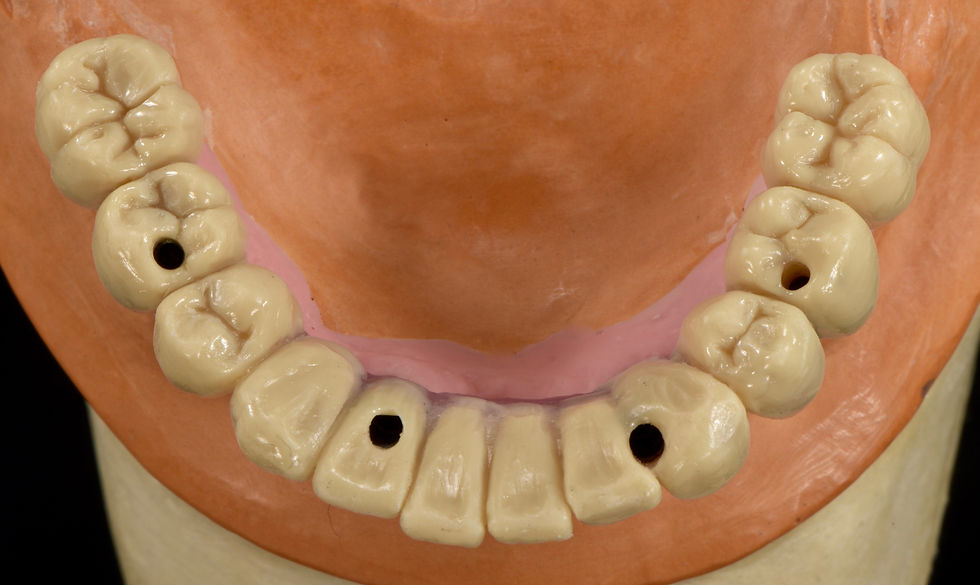

Occlusal view of the lower Toronto Bridge: screw passages are in favourable prosthetic positions